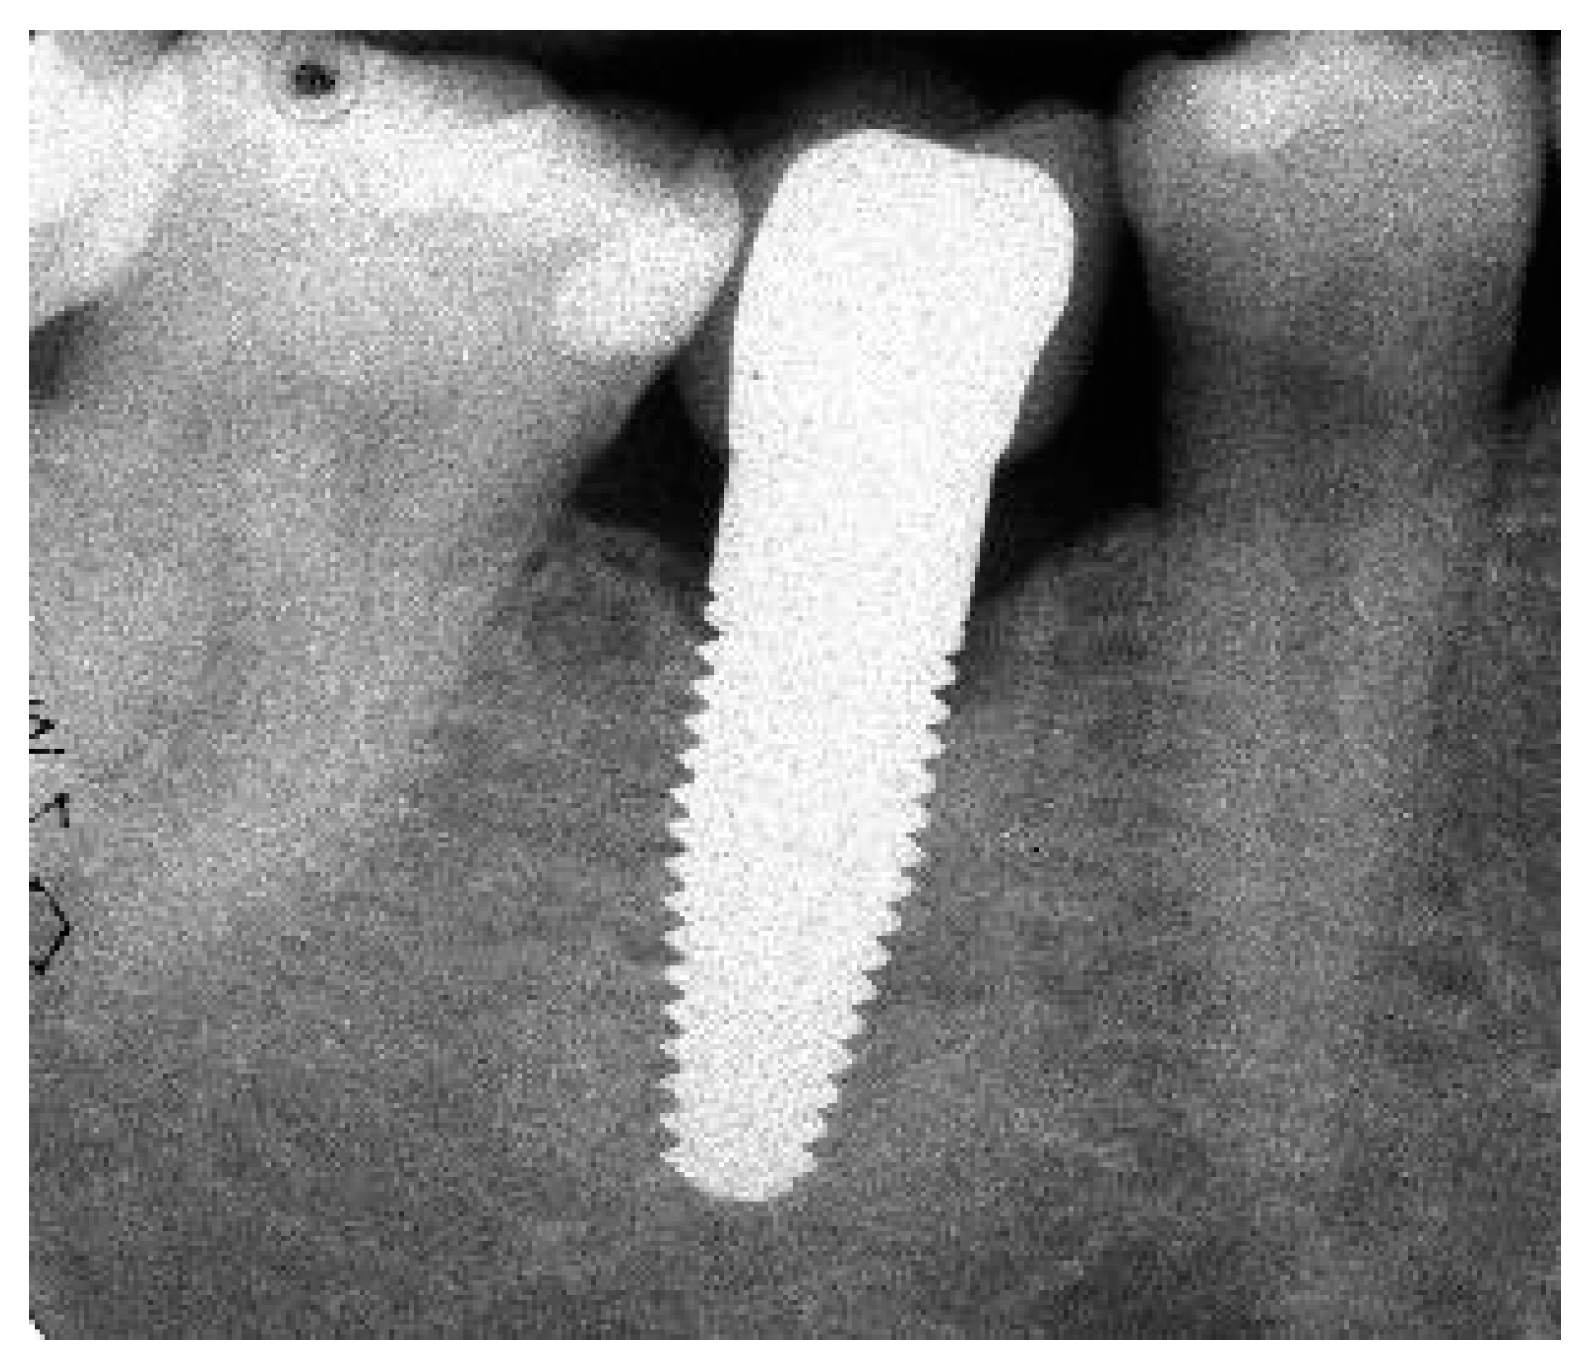

Appendix A. Exemplary Photographs and Radiographs from a Patient at Different Examination Time Points and a Positive Outcome